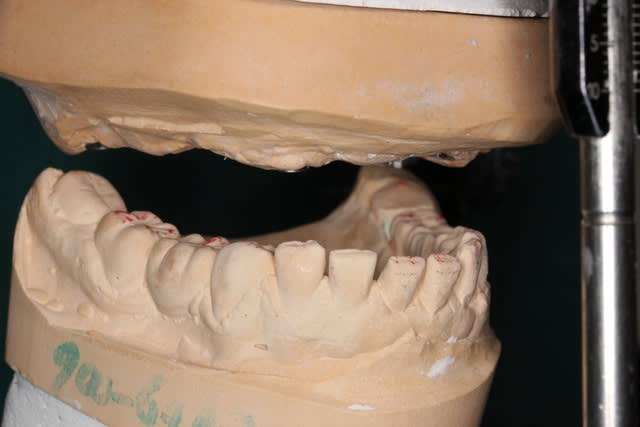

Ou encore...un peu de travail comme Ceramik l aime ;-)))

Pp

PS pour le cas 10 implants en haut et 3 en bas, les questions sont les bienvenues :-))))))) pcq j ai pas vraiment agi ds l ordre logique habituel

Absolument pas perdu les cours de paro

Suivra implanto totale haut et bas

Pour le haut, les incisives bougaient tellement que j ai dû commencer par régler le secteur antérieur de 5 à 5

Ensuite je vais virer les molaires avec PRFs puis ostéotension et poser des implants distaux que je relierai aux implants antérieurs qd ils seront intégrés